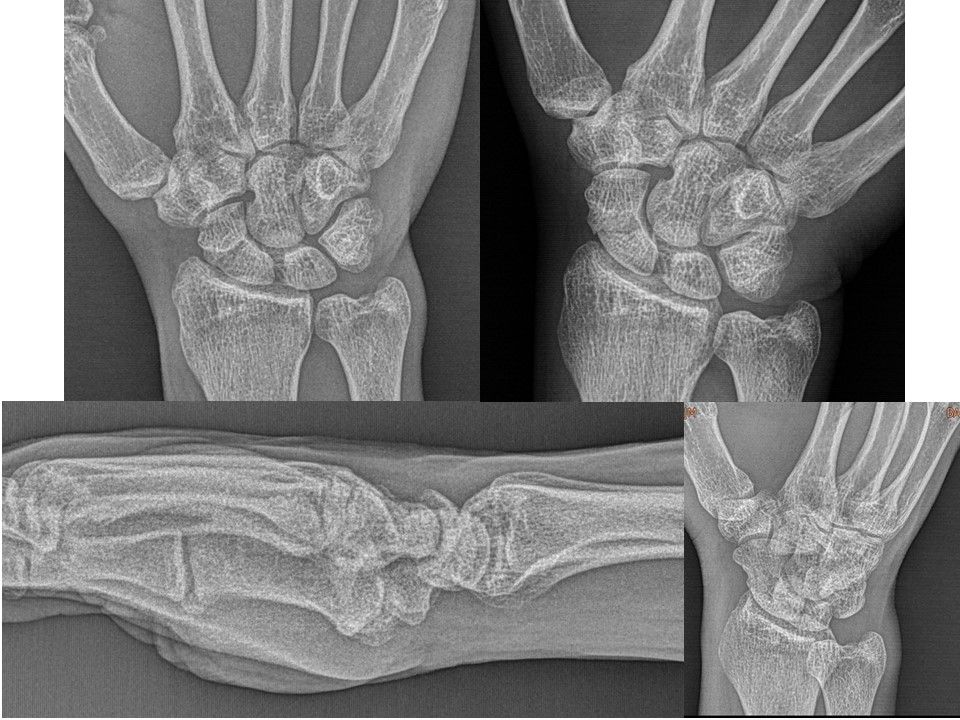

Case 11 - SL Ayrışma